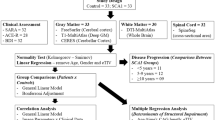

The spinocerebellar ataxias (SCAs) are a genetically heterogeneous group of cerebellar degenerative disorders, characterized by progressive gait unsteadiness, hand incoordination, and dysarthria. The mutational mechanism in SCA1, a dominantly inherited form of SCA, consists of an expanded trinucleotide CAG repeat. In SCA1, there is loss of Purkinje cells, neuronal loss in dentate nucleus, olives, and pontine nuclei. In the present study, we sought to apply intrinsic functional connectivity analysis combined with diffusion tensor imaging to define the state of cerebellar connectivity in SCA1. Our results on the intrinsic functional connectivity in lateral cerebellum and thalamus showed progressive organizational changes in SCA1 noted as a progressive increase in the absolute value of the correlation coefficients. In the lateral cerebellum, the anatomical organization of functional clusters seen as parasagittal bands in controls is lost, changing to a patchy appearance in SCA1. Lastly, only fractional anisotropy in the superior peduncle and changes in functional organization in thalamus showed a linear dependence to duration and severity of disease. The present pilot work represents an initial effort describing connectivity biomarkers of disease progression in SCA1. The functional changes detected with intrinsic functional analysis and diffusion tensor imaging suggest that disease progression can be analyzed as a disconnection syndrome.